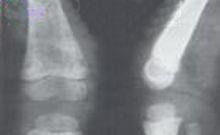

6、X線檢查:無特徵性X線表現,在長期存活病例,由於充脂性組織細胞在骨骼內大量增殖可表現骨質疏鬆、髓腔增寬、骨皮質變薄,甚至長骨可出現局灶性破壞區,但無骨骼膨大畸形改變。嬰兒期以後肺泡受充脂性組織細胞浸潤,肺部可見類似組織細胞增生X症的表現。總之無特異性,僅提供輔助診斷的依據。

3、GM神經節苷酶脂病Ⅰ型:出生即有容貌特徵,前額高、鼻樑低、皮膚粗,50%病例有眼底櫻桃紅斑和淋巴細胞漿有空泡。X線可見多發性骨發育不全,特別是椎骨。